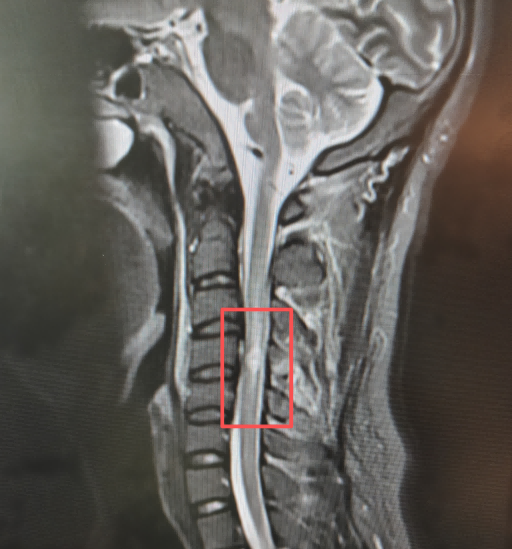

急诊科医生接诊后迅速判断,这不是简单的颈部扭伤,将其转入骨伤二科(脊柱外科)。检查结果显示:颈椎挥鞭样损伤,脊髓已受压水肿。

影像学检查显示,李先生脊髓受压水肿

追尾瞬间,头部剧烈前后甩动,产生的“挥鞭效应”在原有椎管狭窄的基础上,让脊髓狠狠挤压,导致供血受阻、出现水肿,进而引发功能障碍。

刘辉亮主任为李先生制定了精准的方案:双通道下UBE(单侧双通道内镜)减压术。这是一种微创技术。术中,刘辉亮主任、陆泰良主治医师、陈铭俊医师在患者颈后做了两个分别长约1厘米的微小切口,建立工作通道。在内镜清晰可视下,精准地打开了压迫脊髓的“窗户”——用磨钻和咬骨钳去除部分椎板及增厚的黄韧带,为受压的脊髓彻底减压。术中清晰可见椎管狭窄、脊髓水肿,减压后硬脊膜明显膨隆,脊髓搏动恢复。整个过程仅持续约30分钟,出血量极少。